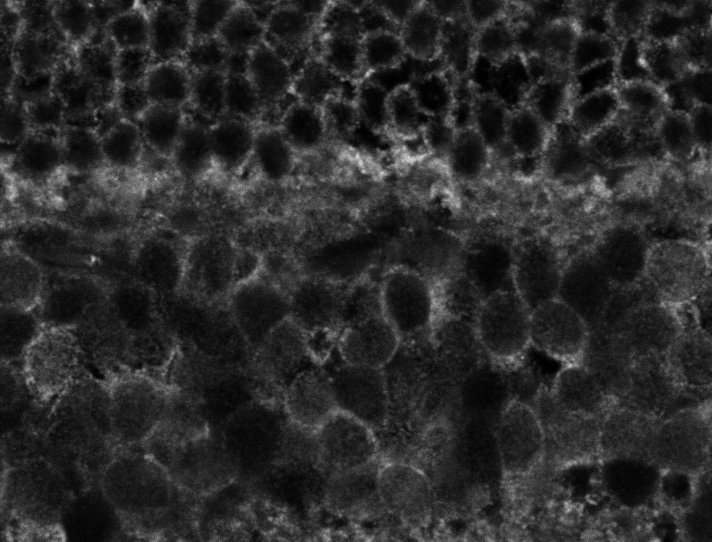

Healthy Eye

Overview 1